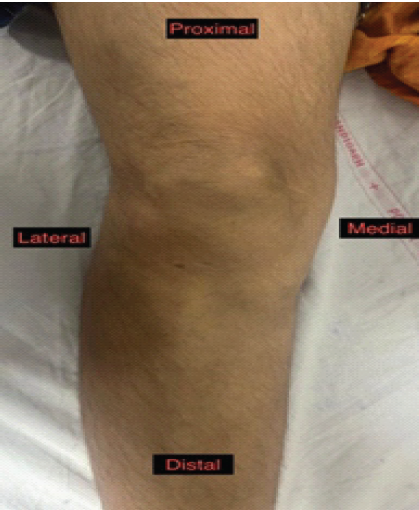

A 50-year-old female, resident of Himachal Pradesh, India, presented to the orthopedics outpatient department with complaints of persistent pain and swelling in the right knee for the past 6 months (Fig. 1).

Figure 1: Clinical photograph showing swelling over the anterior aspect of the right knee, predominantly in the prepatellar region, consistent with bursitis. The swelling was soft and mildly tender.

On physical examination, a diffuse swelling was noted over the anterior aspect of the right knee, predominantly in the prepatellar region. The swelling was soft, mildly tender, non-fluctuant, and not adherent to the overlying skin or underlying structures. There were no signs of inflammation, ulceration, or discharge. Knee joint range of motion was slightly restricted due to discomfort and pain beyond 90° of flexion. There was no neurovascular deficit distally.